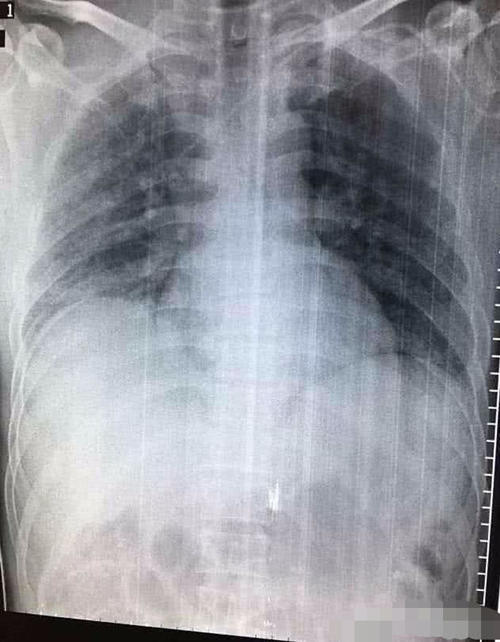

但是俗话说得好,人无完人,药无完药,百草枯有一个致命的缺点,就是对人的毒性非常大,并且无药可解,喝上一口必死无疑!人喝下百草枯后,会迅速被消化道吸收,进入血液中,随着血液到达各个脏器,对脏器造成严重损伤。尤其是肺部,百草枯含量高于血液中十几倍甚至几十倍,会导致肺部组织纤维化,失去呼吸功能,患者最终呼吸衰竭而死。

也就是说,喝了百草枯的人最后都是被活活憋死的。据医生透露,刚送到医院的患者没有什么严重的症状,跟正常人无异,但是一般不超过一个星期就会肺部纤维化而死亡。所以很多人说,百草枯给了你后悔的时间,却不给你活着的机会!